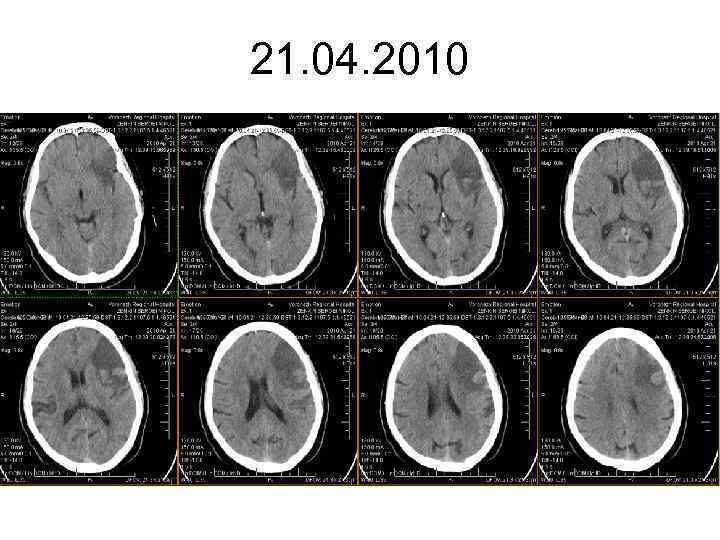

21. 04. 2010